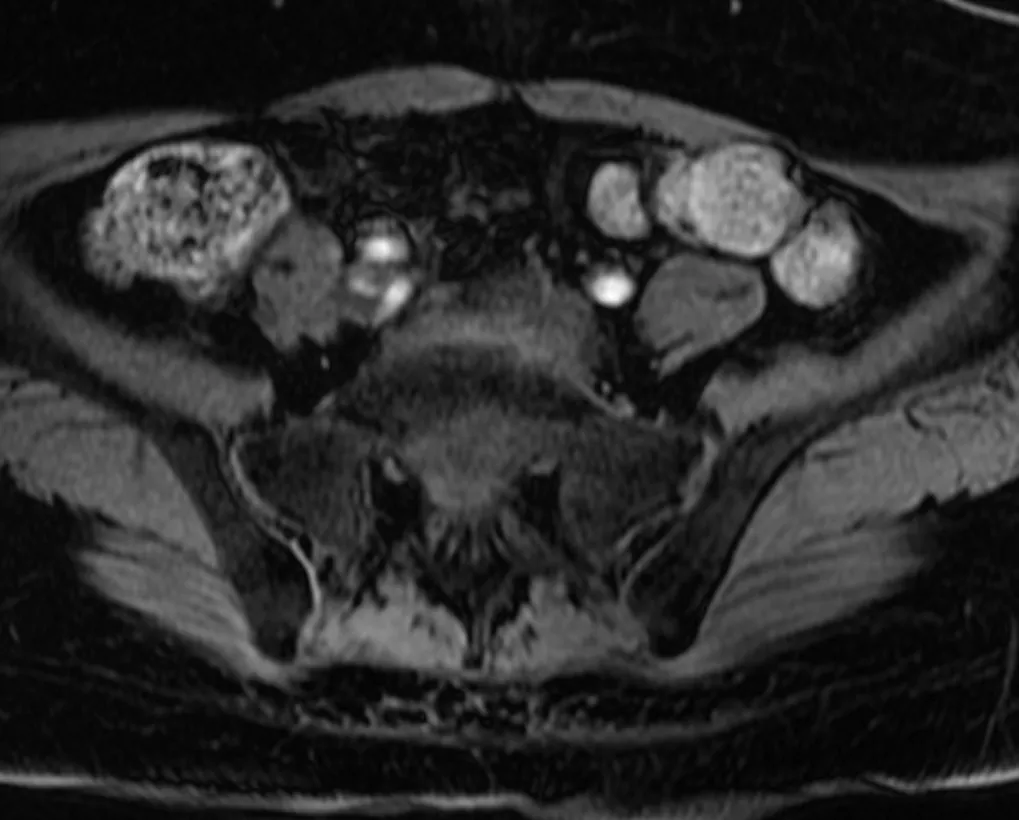

追加の病歴聴取で先行感染症歴や慢性的な下痢や血便なし。身体所見では全身に皮疹は認めず、爪の変形なし。血液検査ではリウマトイド因子陰性、抗CCP抗体陰性、抗核抗体陰性。HLA-B27は陰性。関節超音波検査で末梢関節に滑膜炎や付着部炎は認めず。単純X線で仙腸関節に明らかなびらん、骨硬化、狭小化なし(写真2)。仙腸関節CTでは右仙腸関節にびらん及び骨硬化を示唆する所見あり(写真3)。

写真3 仙腸関節CT 水平断 冠状断